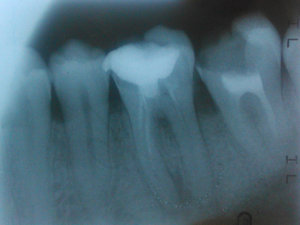

Отвалилась старая пломба, которую ставили девять лет назад. Пришел к стоматологу, она осмотрев сказала, что надо зачистить и заново запломбировать. Начав процедуру чистки, она попробовала пошатать зуб, потом сказала, что нужно сделать снимок. Снимок сделали, ее вердикт — надо удалять зуб, поскольку пошло воспаление вокруг корней, если его лечить со штифтами или еще как, через некоторое время он снова даст о себе знать и все равно придется удалить.